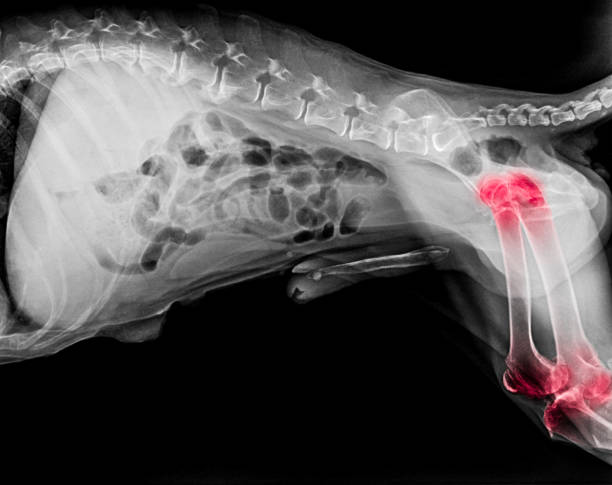

Arthrose: Was genau ist das? <br /><br />Arthrose ist eine Erkrankung der Gelenke, die durch die fortschreitende Zerstörung des Knorpels gekennzeichnet ist. <br />Diese Krankheit ist schmerzhaft und kann für dein Haustier sehr behindernd werden. <br />Das Risiko einer Arthrose steigt mit dem Alter. <br />Große Hunde sind aufgrund ihrer Morphologie und ihres Gewichts anfälliger für diese Krankheit. <br /><br />Um das Risiko einer Arthrose zu verringern, achte auf die Ernährung deines Hundes. <br />Sein Gewicht ist ein entscheidender Faktor. <br />Regelmäßige körperliche Aktivität trägt auch zur Stärkung des Knorpels bei. <br /><br />Wie kann ich die Krankheit bei meinem Hund erkennen? <br />Stufe 1: Dein Hund humpelt und wirkt beim Bewegen steif. <br />Stufe 2: Das Tier weint wegen der Schmerzen und kann zögern, wenn du eine schmerzhafte Stelle berührst. <br />Stufe 3: Seine Glieder sind blockiert. Der Hund ist gelähmt und kann sich nicht mehr bewegen. <br /><br />Diese Symptome sind besonders auffällig beim Aufwachen oder nach längerer Zeit ohne Bewegung. <br />Entzündungshemmende Medikamente können dein Haustier jedoch entlasten. <br />Osteopathie, Elektrostimulierung, Massage und Schwimmen können Abhilfe schaffen!